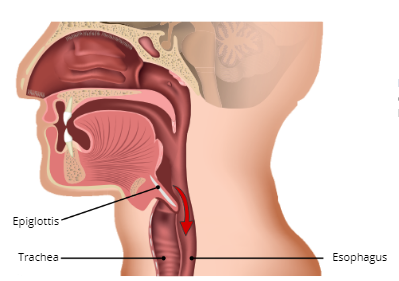

Epiglottis

a small, leaf-like flap of cartilage at the bottom of the laryngopharynx that prevents food from entering the trachea or lungs

Trachea

AKA windpipe is a C-shaped ringed cartilaginous tube

Function of Trachea

To warm and moisten the air before entering the lungs and serve as a passageway for air from the upper respiratory tract to the lungs